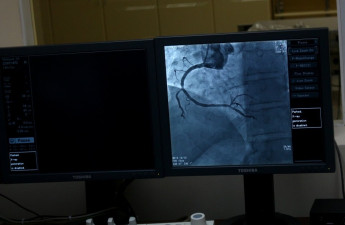

Луцька міська лікарня потребує 2,5 мільйона на оновлення обладнання

Трубка для ангіографу, за допомогою якого рятують життя сотням волинян, потребує заміни. Виділити понад 2 мільйони на оновлення високоспеціалізованого медичного обладнання міська клінічна лікарня просить з міського бюджету Луцька